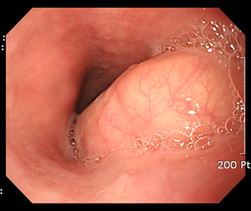

Figure 4 A large esophageal subepithelial tumor (SET).

An esophagogstroduodenoscopy (EGD) showed a large (3.5 cm) SET at mid esophagus.